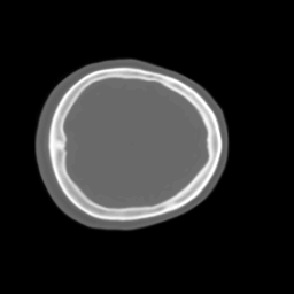

Model-based treatment planning for transcranial ultrasound therapy typically involves mapping the acoustic properties of the skull from an x-ray computed tomography (CT) image of the head. Here, three methods for generating pseudo-CT images from magnetic resonance (MR) images were compared as an alternative to CT. A convolutional neural network (U-Net) was trained on paired MR-CT images to generate pseudo-CT images from either T1-weighted or zero-echo time (ZTE) MR images (denoted tCT and zCT, respectively). A direct mapping from ZTE to pseudo-CT was also implemented (denoted cCT). When comparing the pseudo-CT and ground truth CT images for the test set, the mean absolute error was 133, 83, and 145 Hounsfield units (HU) across the whole head, and 398, 222, and 336 HU within the skull for the tCT, zCT, and cCT images, respectively. Ultrasound simulations were also performed using the generated pseudo-CT images and compared to simulations based on CT. An annular array transducer was used targeting the visual or motor cortex. The mean differences in the simulated focal pressure, focal position, and focal volume were 9.9%, 1.5 mm, and 15.1% for simulations based on the tCT images, 5.7%, 0.6 mm, and 5.7% for the zCT, and 6.7%, 0.9 mm, and 12.1% for the cCT. The improved results for images mapped from ZTE highlight the advantage of using imaging sequences which improve contrast of the skull bone. Overall, these results demonstrate that acoustic simulations based on MR images can give comparable accuracy to those based on CT.